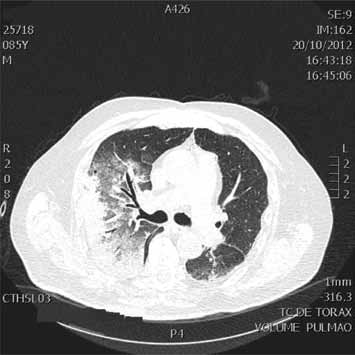

Considere um paciente do sexo masculino, 85 anos, com antecedentes de fibrilação atrial crônica, doença pulmonar obstrutiva crônica e hidrocefalia de pressão normal com implante de derivação ventriculoperitoneal (DVP) há 1 ano, após episódio de alteração progressiva da marcha e confusão mental à época. Não apresentava outros antecedentes ou alterações laboratoriais e fazia uso apenas de broncodilatador associado com corticoide inalatório. Familiares relatam que, há cerca de 15 dias, o paciente apresentou forte quadro gripal, queda do estado geral, prostração e episódios de engasgos frequentes, com alimentos líquidos. Há 2 dias passou a apresentar tosse produtiva com expectoração esverdeada, febre de 38 graus e piora da adinamia com inapetência acentuada, deixando inclusive de ingerir líquidos. Foi trazido ao pronto-atendimento em mau estado geral, sonolento, taquipneico com respiração superficial, desidratado e com leve cianose de extremidades. Sua pressão arterial era de 120x60 mmHg, FC = 120 bpm, T = 37,5 graus. A ausculta pulmonar evidenciava tempo expiratório prolongado e sibilos ins e expiratórios. Ausculta cardíaca com ritmo irregular e ausência de sopros. Sem outras alterações ao exame físico. Foi submetido a um exame de tomografia do tórax e um dos cortes tomográficos encontra-se ilustrado a seguir.

enunciado 925223-1